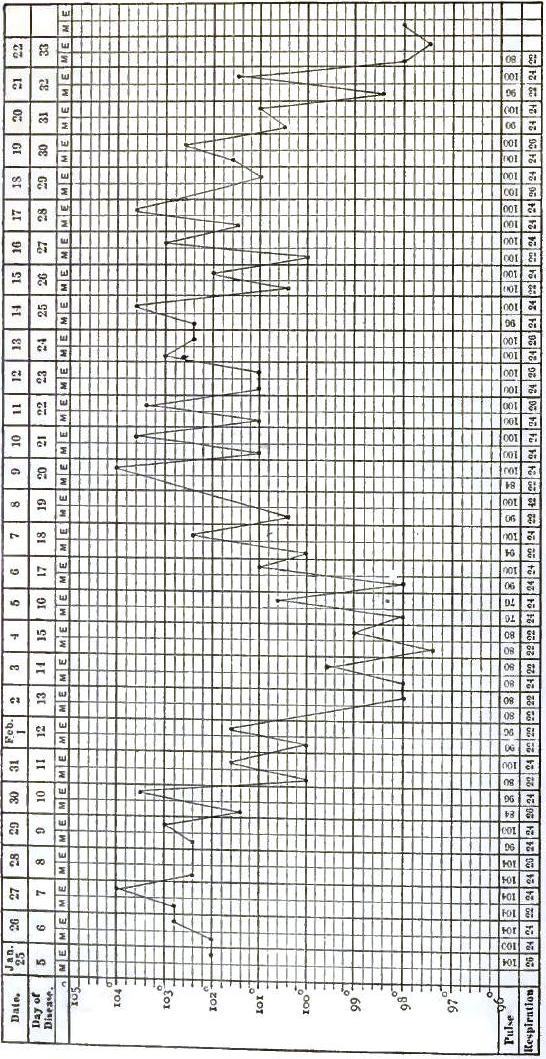

| 17. | CHART OF TEMPERATURE IN TYPHOID FEVER WITH RELAPSE.—RELAPSE |

| 18. | TEMPERATURE CHART OF TYPHOID FEVER.—ABORTIVE ATTACK, FOLLOWED BY TYPICAL ATTACK |

| 19. | SPIRILLUM FROM THE BLOOD IN A CASE OF RELAPSING FEVER |

| 20. | TEMPERATURE CHART OF TYPICAL CASE OF RELAPSING FEVER, WITH THREE RELAPSES TERMINATING IN RECOVERY |

| 21. | TEMPERATURE CHART OF TYPICAL CASE OF RELAPSING FEVER, TERMINATING IN RECOVERY |

| 22. | TEMPERATURE CHART FROM A CASE OF THE BILIOUS TYPHOID OR GRAVE SUBINTRANT FORM OF RELAPSING FEVER |

| 23. | TEMPERATURE CHART SHOWING THE LAPSE OF A REMITTENT FEVER INTO AN INTERMITTENT |

| 24. | CHARTS SHOWING THE TEMPERATURE CURVE IN TYPHO-MALARIAL FEVER: PART I., SHOWING PREDOMINANCE OF TYPHOIDAL ELEMENT; PART II., SHOWING PREDOMINANCE OF MALARIAL ELEMENT |